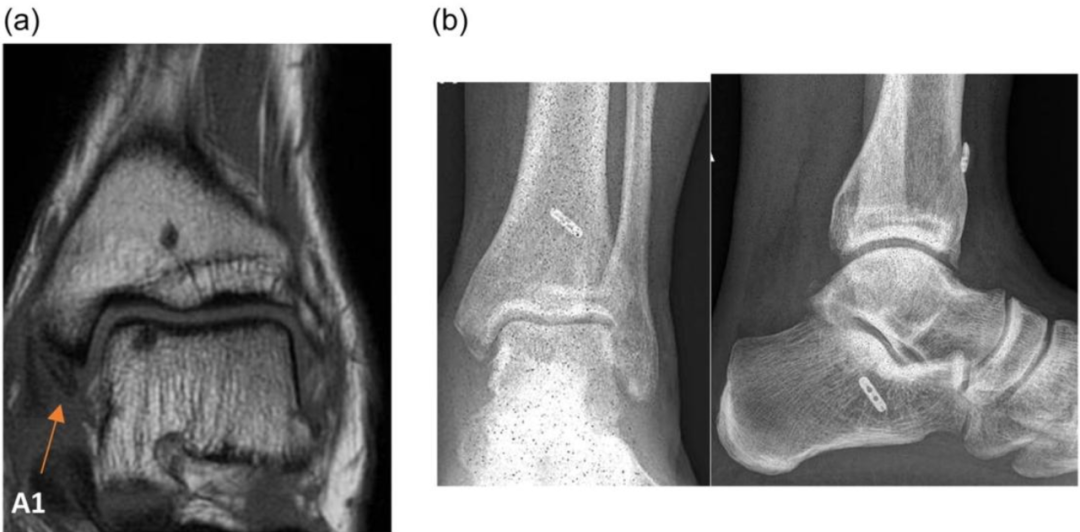

图a,MRI扫描显示慢性三角韧带断裂(A1)。图b,使用自体肌腱移植物进行三角韧带重建。